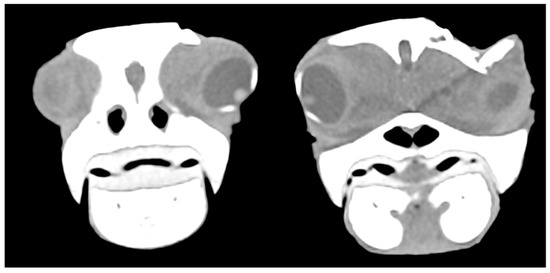

In six cases, the ocular globe was shifted downward due to the pressure of the surrounding tissue resulting in brain contusion and compression of the salt gland. In moderate and mild cases, parietal and postorbital fragments were deeply or superficially depressed, respectively (Figure 8).

Figure 8. CT scan showing the displacement of the eyeball downwards due to the pressure of the surrounding tissue and fractured postorbital bone.